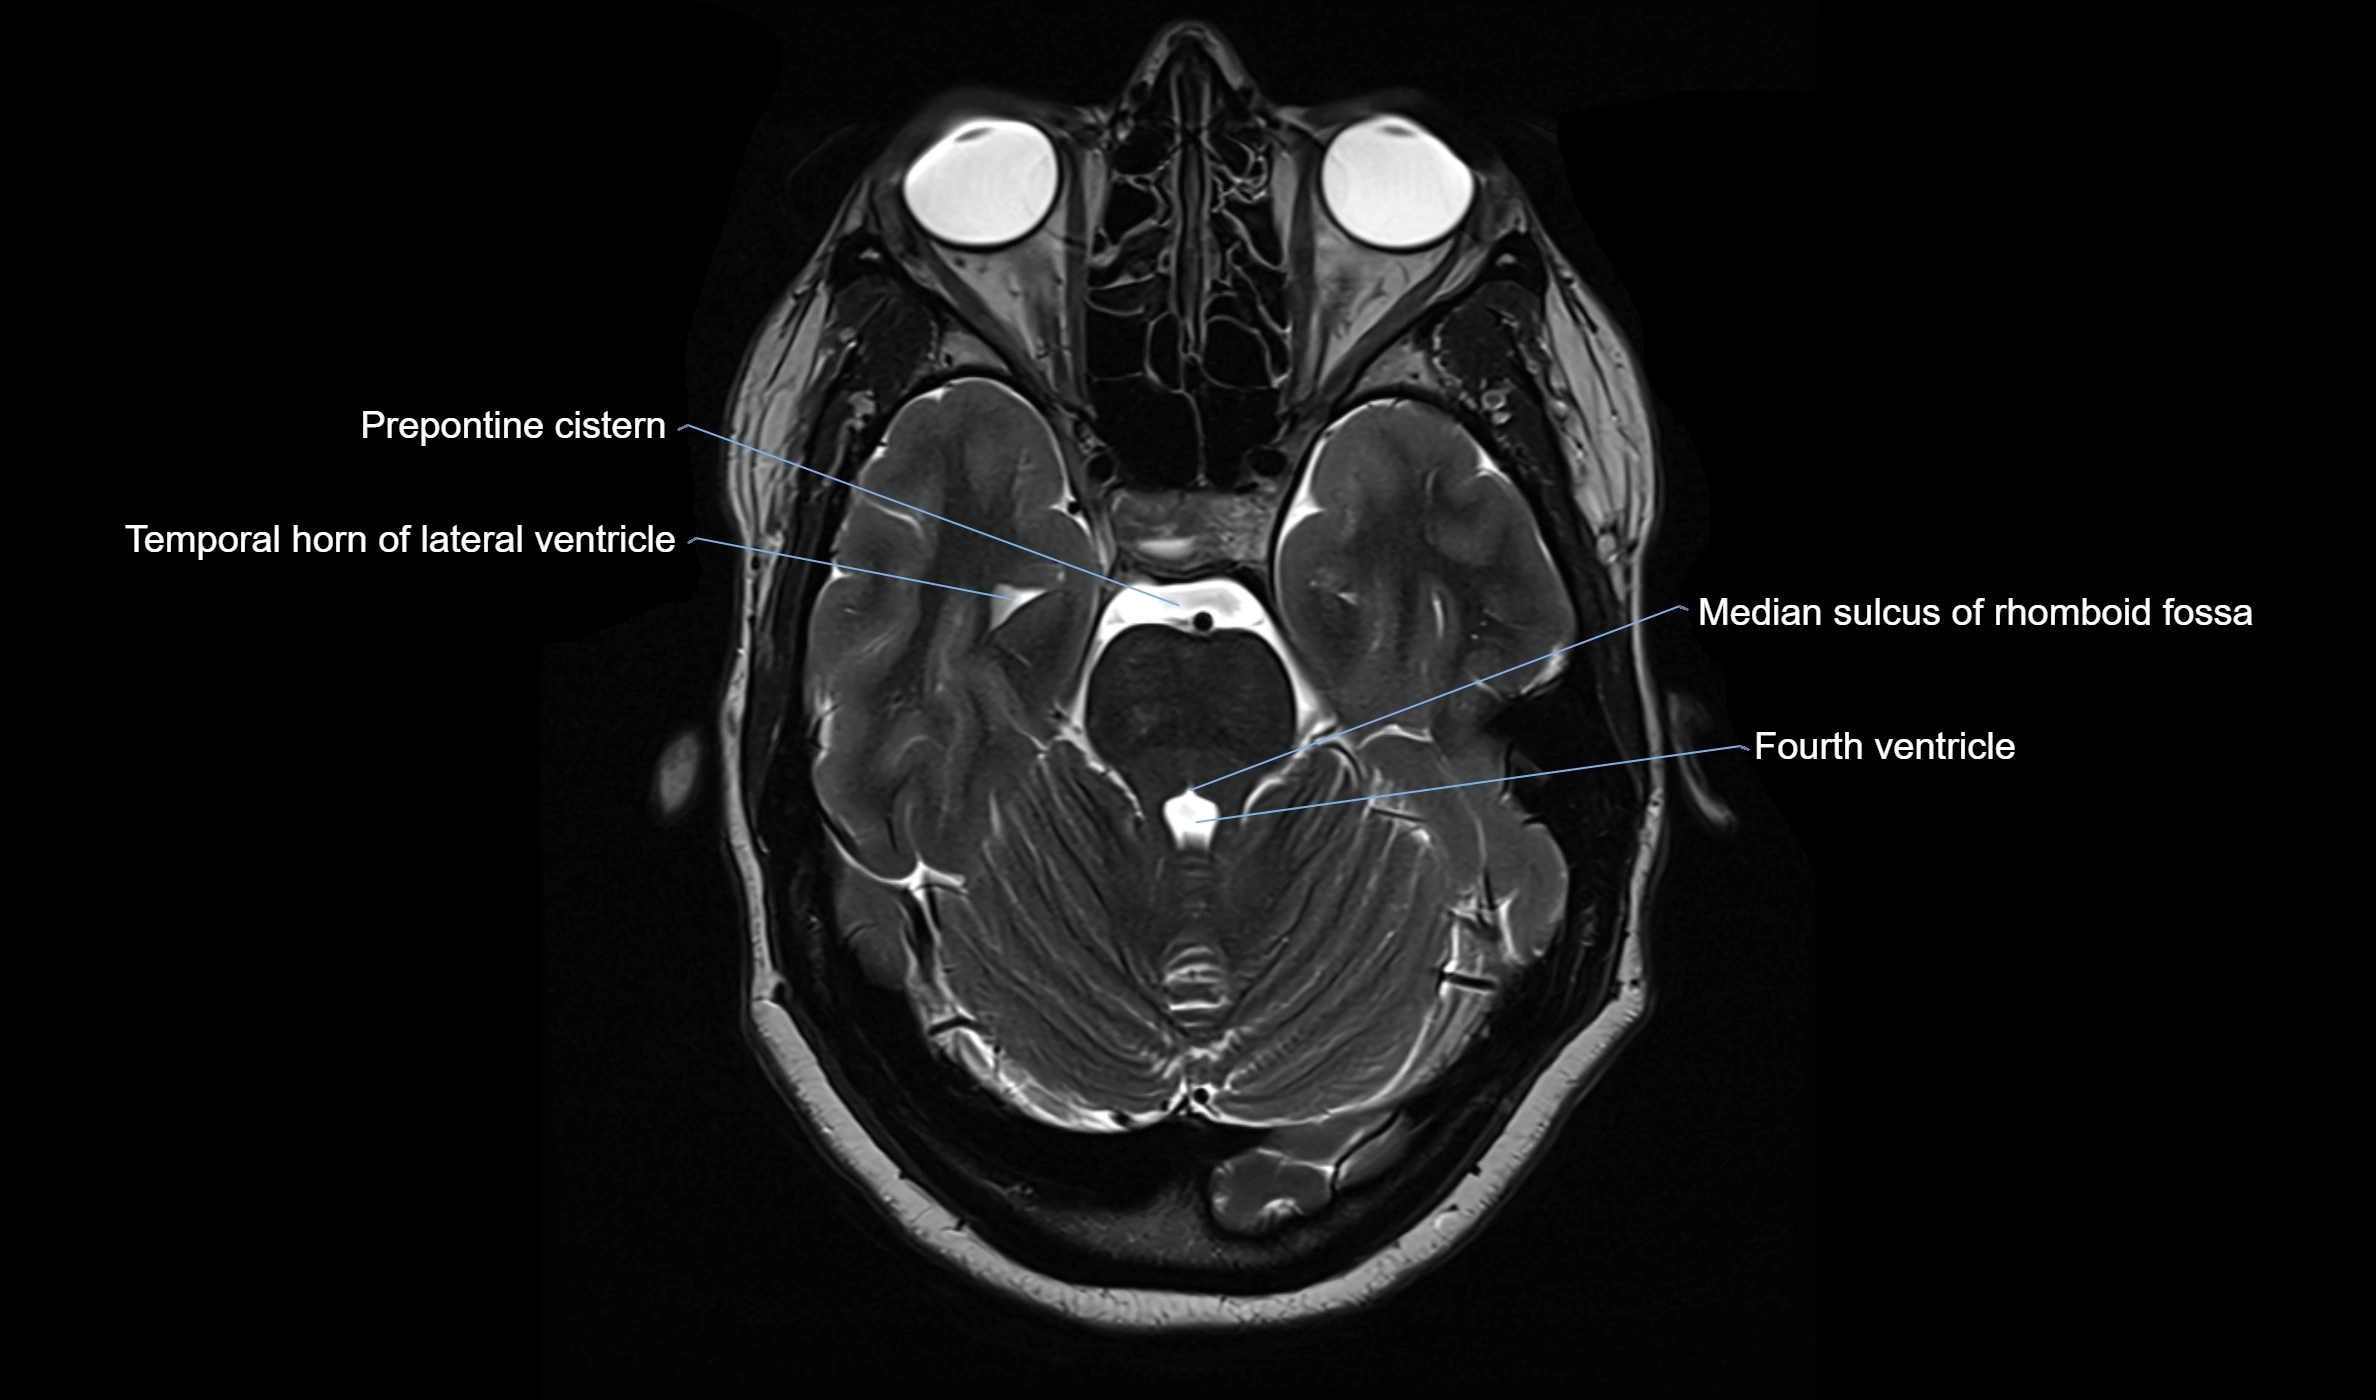

MRI images

image